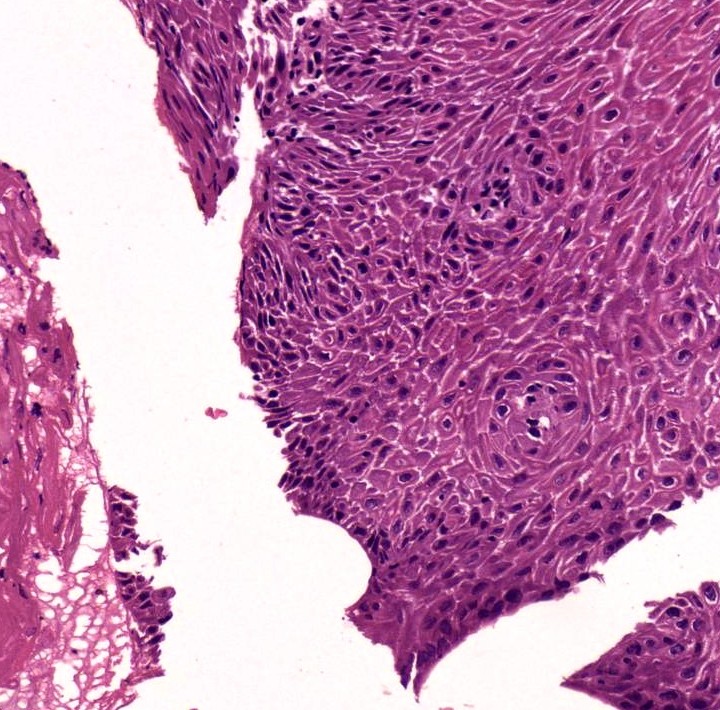

Supreme Image Quality and Intuitive User Experience